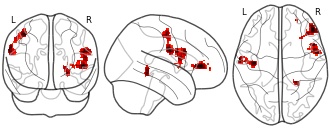

"name": "Multi_VBMgreater_fMRIenhanced",

"description": "Multi-modal analysis in BPD. Brain regions exhibiting greater gray matter and enhanced activation during emotion processing in BPD compared to healthy controls. Note: Results were thresholded at p<.0025. Note2: Results were updated (see Erratum for this publication).",